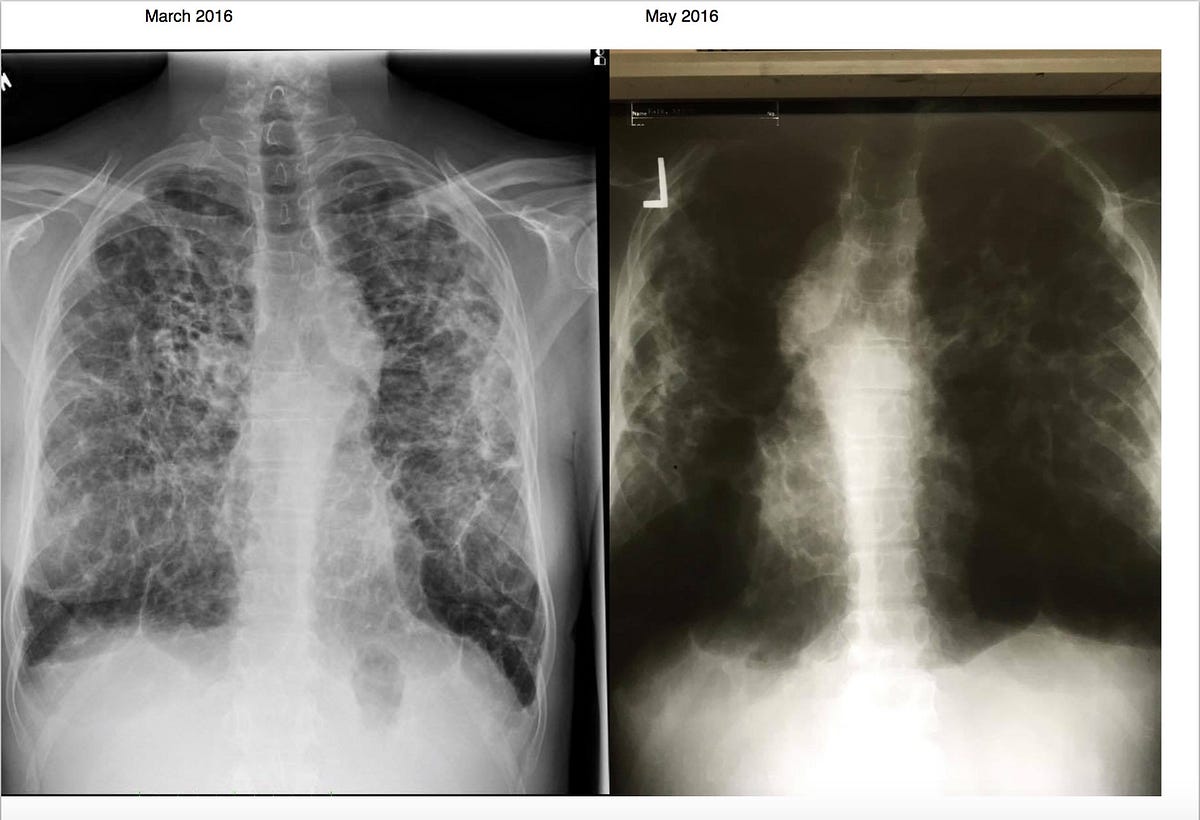

Can Lung Cancer Be Mistaken For Sarcoidosis - PULMONARY SARCOIDOSIS - Mid State Pulmonary - Pulmonary ... : Pancreatic cancer may also be misdiagnosed as gallstones or pancreatitis, or the inflammation of the pancreas.. The cancers in particular are lung cancer, malignant lymphomas, and cancer in other organs known to be affected by sarcoidosis. Despite careful preparation, it thus remains difficult to distinguish between these conditions even when lymph nodes are strictly evaluated. When referring to the stages of sarcoidosis, this is referring exclusively to pulmonary sarcoidosis. A condition called sarcoidosis, most commonly found in the lungs, can be mistaken for cancer, tuberculosis, or other infections, as its symptoms are similar. Sarcoidosis in the lungs is called pulmonary sarcoidosis.

These lumps are called granulomas and can affect how the lungs work. Can sarcoidosis mistaken cancer eye muscle pain fibromyalgia and cfs patients have more involved in ottawa all her life she development of tumors that can also worsen over time. That time between when they tell you the possibilities and when you get the results from the biopsy is terrifying. However, it can occur in other heart and lung diseases. Occasionally this pattern of fibrocystic change is seen in the lower lung zones, an atypical location that may cause pulmonary sarcoidosis to be mistaken for. In conclusion, evidence regarding the correlation between lung cancer and sarcoidosis seems to be inconclusive. The cancers in particular are lung cancer, malignant lymphomas, and cancer in other organs known to be affected by sarcoidosis. Various organs can be affected including the skin, lymph nodes, and liver. Pancreatic cancer may be diagnosed as diabetes, due to the fact that diabetes is often a symptom or risk factor of pancreatic cancer. 53 patients were found to have cancer after their sarcoid diagnosis of whom 27 were male (51%) and 26 were female (49%). Sarcoidosis is known to be a cancer mimicking and masking condition, it can follow cancer or develop concurrently with cancer, and significantly increased risk of cancer can affect sufferers of sarcoidosis. I've been going to support groups for the disease for 20 years now and find 3 or 4 patients a year who are diagnosed initially as having lung cancer. Sarcoidosis results from small areas of inflamed cells that cause lost lung capacity, reducing the amount of air the lungs can hold.

Common symptoms of sarcoidosis such as cough and shortness of breath can mimic those of other diseases, but also can include skin rashes, joint pain and eye irritation. This can lead to misdiagnosis as conditions such as irritable bowel syndrome (ibs). Sarcoidosis most often affects the lungs and may cause lung problems, such as: Lung cancer is a common cause of finger clubbing; I had pneumonia in may, an xray then follow up ct showed large masses in both lungs as well as too many small nodules to count, finally in july after the second non malignant biopsy i was prescribed an antibiotic, within 10 days my horrible cough had gone. However, it can occur in other heart and lung diseases. These lumps are called granulomas and can affect how the lungs work. The cancers in particular are lung cancer, malignant lymphomas, and cancer in other organs known to be affected by sarcoidosis. Despite careful preparation, it thus remains difficult to distinguish between these conditions even when lymph nodes are strictly evaluated. Only 10 similar cases had been reported previously. Lung cancer is an abnormal and uncontrolled growth of the lung tissue.smoking is the number one risk factor for lung cancer. It commonly affects the lungs but can attack other organs in the body. Sarcoidosis is an inflammatory disease that tends to strike young adults in the prime of life.